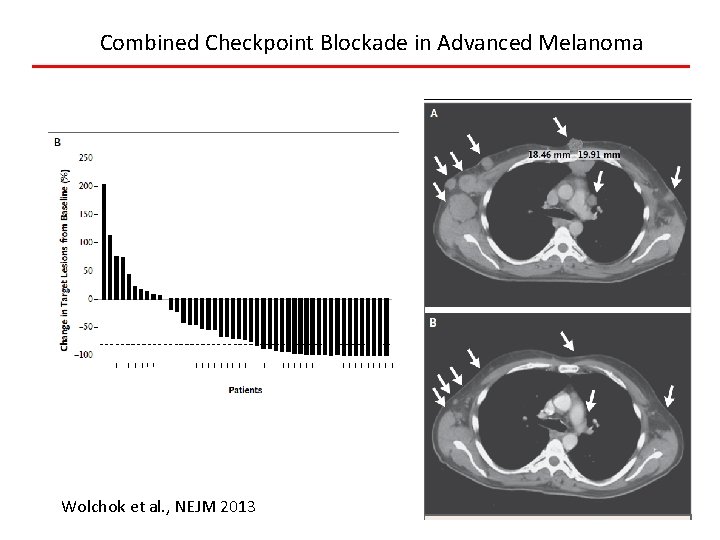

Combined Checkpoint Blockade in Advanced Melanoma Wolchok et al. , NEJM 2013